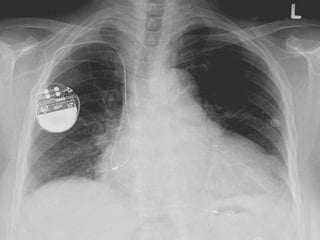

• O gerador do marca-passo - a caixa metálica que é composta

pelos componentes eletrônicos e pela bateria - fica logo

abaixo da pele do tórax, entre a gordura e o músculo peitoral.

• Os eletrodos, conectados a esta caixa são amarrados à

musculatura e têm sua extremidade mais distal fixada ao

músculo cardíaco.

• Após a limpeza rigorosa da região peitoral do lado esquerdo ou direito,

o local abaixo da clavícula recebe anestesia local e é feita uma pequena

incisão. Em seguida, o eletrodo do marca passo é cuidadosamente

introduzido por uma veia até o coração. O médico monitora o

posicionamento correto do eletrodo no coração por meio de um sistema

de raios X.

• Depois de testar a posição e o funcionamento do eletrodo, ele é

conectado ao marcapasso, que é implantado em uma pequena “bolsa”

sob da pele. Para finalizar, o médico fecha o local da incisão.